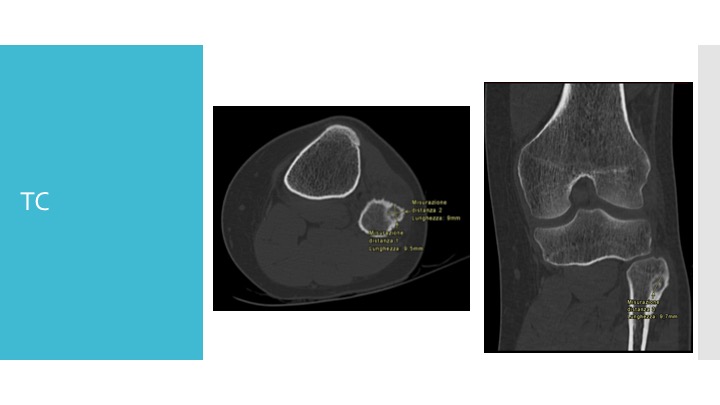

- TAC: è una radiografia più dettagliata che fornisce immagini tridimensionali dell’osso.